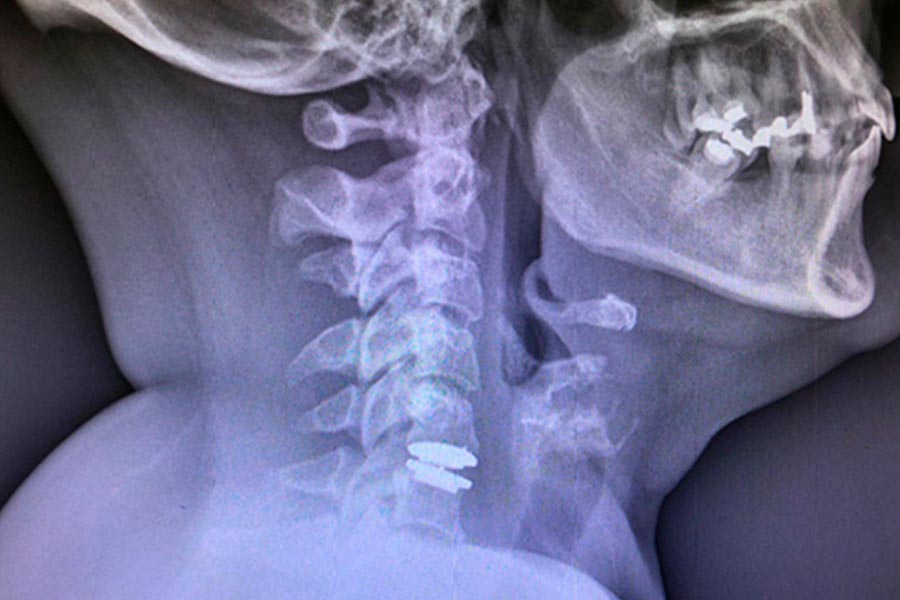

En este caso clínico, los especialistas del Instituto de Cirugía Avanzada de Columna intervienen a una paciente joven mediante artrodesis cervical.

Es un caso de cirugía cervical de una paciente de mediana edad que fue operada hace aproximadamente 6 años.

La paciente presenta varias hernias discales cervicales, empeoradas por la presencia de artrosis en la zona y que provoca dolencias en el lado derecho (brazos y cuello).

El paciente acude a la consulta tras sufrir fuertes dolores en la zona, provocados por una artrodesis no efectiva. Implante de prótesis cervical.